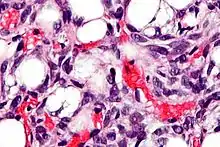

Lipoblasts (white arrow) and lipocytes (black arrow), in a case of lipoblastoma

Lipoblasts are seen in liposarcoma[5][6] and characteristically have abundant multivacuolated clear cytoplasm and a dark staining (hyperchromatic), indented nucleus.